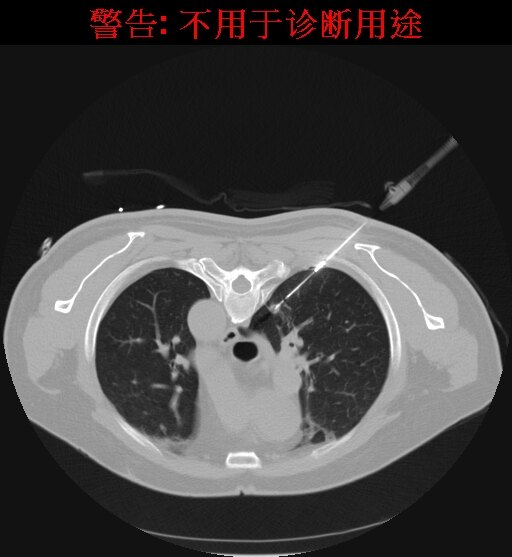

针道消融模式下拔出射频消融电极,结节周围可见晕征包绕,消融满意,无并发症。